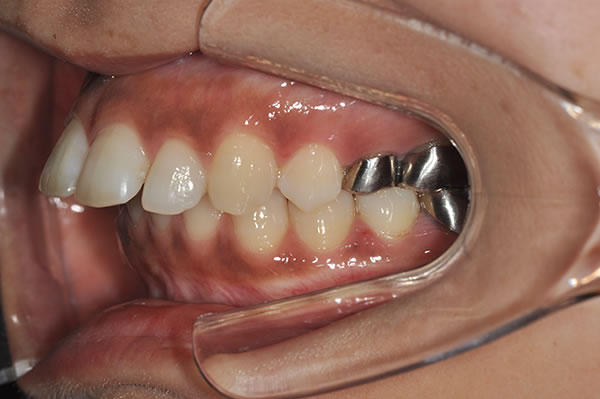

上顎前突症の治療例

上顎前突症(出っ歯)の矯正症例 ケース01

| 治療前(初診) | 治療後 | |